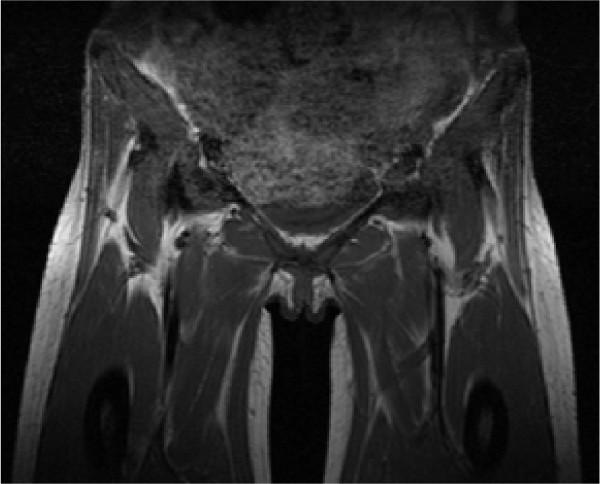

We report the case of a 44-year-old Afro-Caribbean woman with homozygous sickle cell disease who presented with chest crisis and later developed pyomyositis of her hip and pelvic muscles. Salmonella agbeni was isolated from blood cultures and magnetic resonance imaging confirmed the diagnosis in this case. It is noteworthy of this case that there were no antecedent signs of gastroenteritis. Drainage was not appropriate and she was treated with intravenous antibiotics for six weeks.

Focal Salmonella infections are uncommon in soft tissue. Pyomyositis should be considered in patients with sickle cell anemia that continue to have muscle pain and high fevers, despite initial management of their sickle cell crisis. Radiological imaging, particularly magnetic resonance imaging, is a crucial tool in establishing the diagnosis.

我们报告一例44岁的非洲加勒比裔女性,患有纯合子镰状细胞病,最初表现为胸部危象,随后发展为臀部和骨盆肌肉的脓性肌炎。血液培养分离出阿贝尼沙门氏菌,磁共振成像确诊了该病例。该病例值得注意的是没有前期胃肠炎的迹象。引流不合适,她接受了六周的静脉抗生素治疗。

局灶性沙门氏菌感染在软组织中并不常见。对于镰状细胞贫血患者,尽管对镰状细胞危象进行了初始治疗,但如果持续存在肌肉疼痛和高热,应考虑脓性肌炎。放射学成像,尤其是磁共振成像,是确立诊断的关键工具。